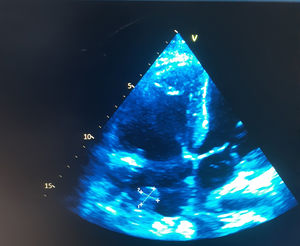

Se realizó ecocardiograma transtorácico que mostró aurícula izquierda de 41mm, fracción de eyección del ventrículo izquierdo del 52%, espesores septal y posterior de 15 y 13mm respectivamente, compatibles con hipertrofia concéntrica limítrofe. Se evidenció disfunción diastólica con retardo en la relajación y aumento de las presiones de llenado, insuficiencia mitral, aórtica y tricuspídea leves, así como hipertensión pulmonar leve. El hallazgo más relevante fue una imagen nodular de 19 por 16mm en la base de la aurícula derecha, en íntimo contacto con la válvula de Eustaquio, compatible con vegetación. Además, se describió derrame pericárdico leve sin repercusión hemodinámica (fig. 1).

Los hemocultivos de control persistieron positivos para S. aureus en dos tomas posteriores, negativizándose en los controles subsiguientes tras el ajuste del tratamiento antibiótico. Luego de tres semanas de terapia dirigida, el ecocardiograma transtorácico de control mostró persistencia de la imagen nodular adherida a la válvula de Eustaquio, con dimensiones similares a las previamente informadas, sin evidencia de incremento en su tamaño ni de complicaciones adicionales (fig. 2). La paciente completó el esquema de antibióticos endovenosos prolongados, con mejoría progresiva de la disnea y estabilización de los parámetros inflamatorios, motivo por el cual fue dada de alta con tratamiento antibiótico oral para completar tres semanas adicionales con trimetoprim/sulfametoxazol. No se realizó ecocardiografía transesofágica debido a que el ecocardiograma transtorácico ofrecía una ventana acústica adecuada y permitía una visualización satisfactoria de las estructuras implicadas, por lo que se consideró suficiente para el seguimiento.